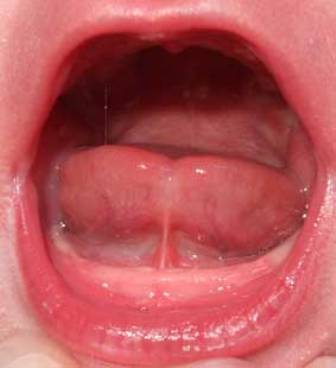

Anquiloglosia significa literalmente “lengua atada o anclada” y es una definición muy gráfica de lo que les pasa a los bebés que nacen con el frenillo de la lengua corto: la lengua se encuentra sujeta al suelo de la boca y no puede realizar los movimientos necesarios para que el bebé pueda mamar de manera eficaz y sin comprometer el bienestar de su madre.

El frenillo lingual se encuentra debajo de la lengua, insertado, de manera ideal, dentro de la lengua. Sin embargo, cuando en etapas embrionarias se desarrolla la cavidad oral y los músculos hiogloso y geniogloso, en ocasiones estos dos músculos se separan mal, quedando el frenillo fuera de la lengua. Esta situación hace que la lengua se mantenga sujeta al suelo de la boca, impidiendo en diferente medida los movimientos de la lengua que permiten al bebé realizar la transferencia de leche: protrusión, elevación, peristaltismo, acanalamiento y lateralización. Todos estos movimientos son necesarios para que el bebé pueda mamar de manera placentera y eficaz y para que posteriormente, al iniciar la alimentación complementaria, pueda realizar los movimientos necesarios para ensalivar y tragar el bolo digestivo con facilidad.

Hay que evaluar el grado de movilidad de la lengua, incluida la capacidad de la misma para extenderse más allá del labio inferior, elevarse hasta el paladar estando la boca bien abierta y efectuar movimientos transversales de una comisura de la boca a la otra sin necesidad de deformarse (lateralización). La elevación parece ser el movimiento lingual que más influye en la lactancia, por lo que debería pesar más que los demás parámetros a la hora de evaluar la anquiloglosia.

La valoración del tipo de frenillo se realiza de manera visual o digital, hay señales que nos indican que el bebé puede tener el frenillo de la lengua corto:

La inserción del frenillo se produce en la punta de la lengua. Cuando el bebé llora, la lengua tiene forma de corazón o parece bífida, ya que el frenillo tira de la punta de la lengua hacia el interior de la boca.

La inserción del frenillo se produce unos milímetros más atrás que el tipo 1. La lengua no se suele ver bífida, pero cuando el bebé llora, se puede observar que la punta de la lengua desciende hacia abajo.